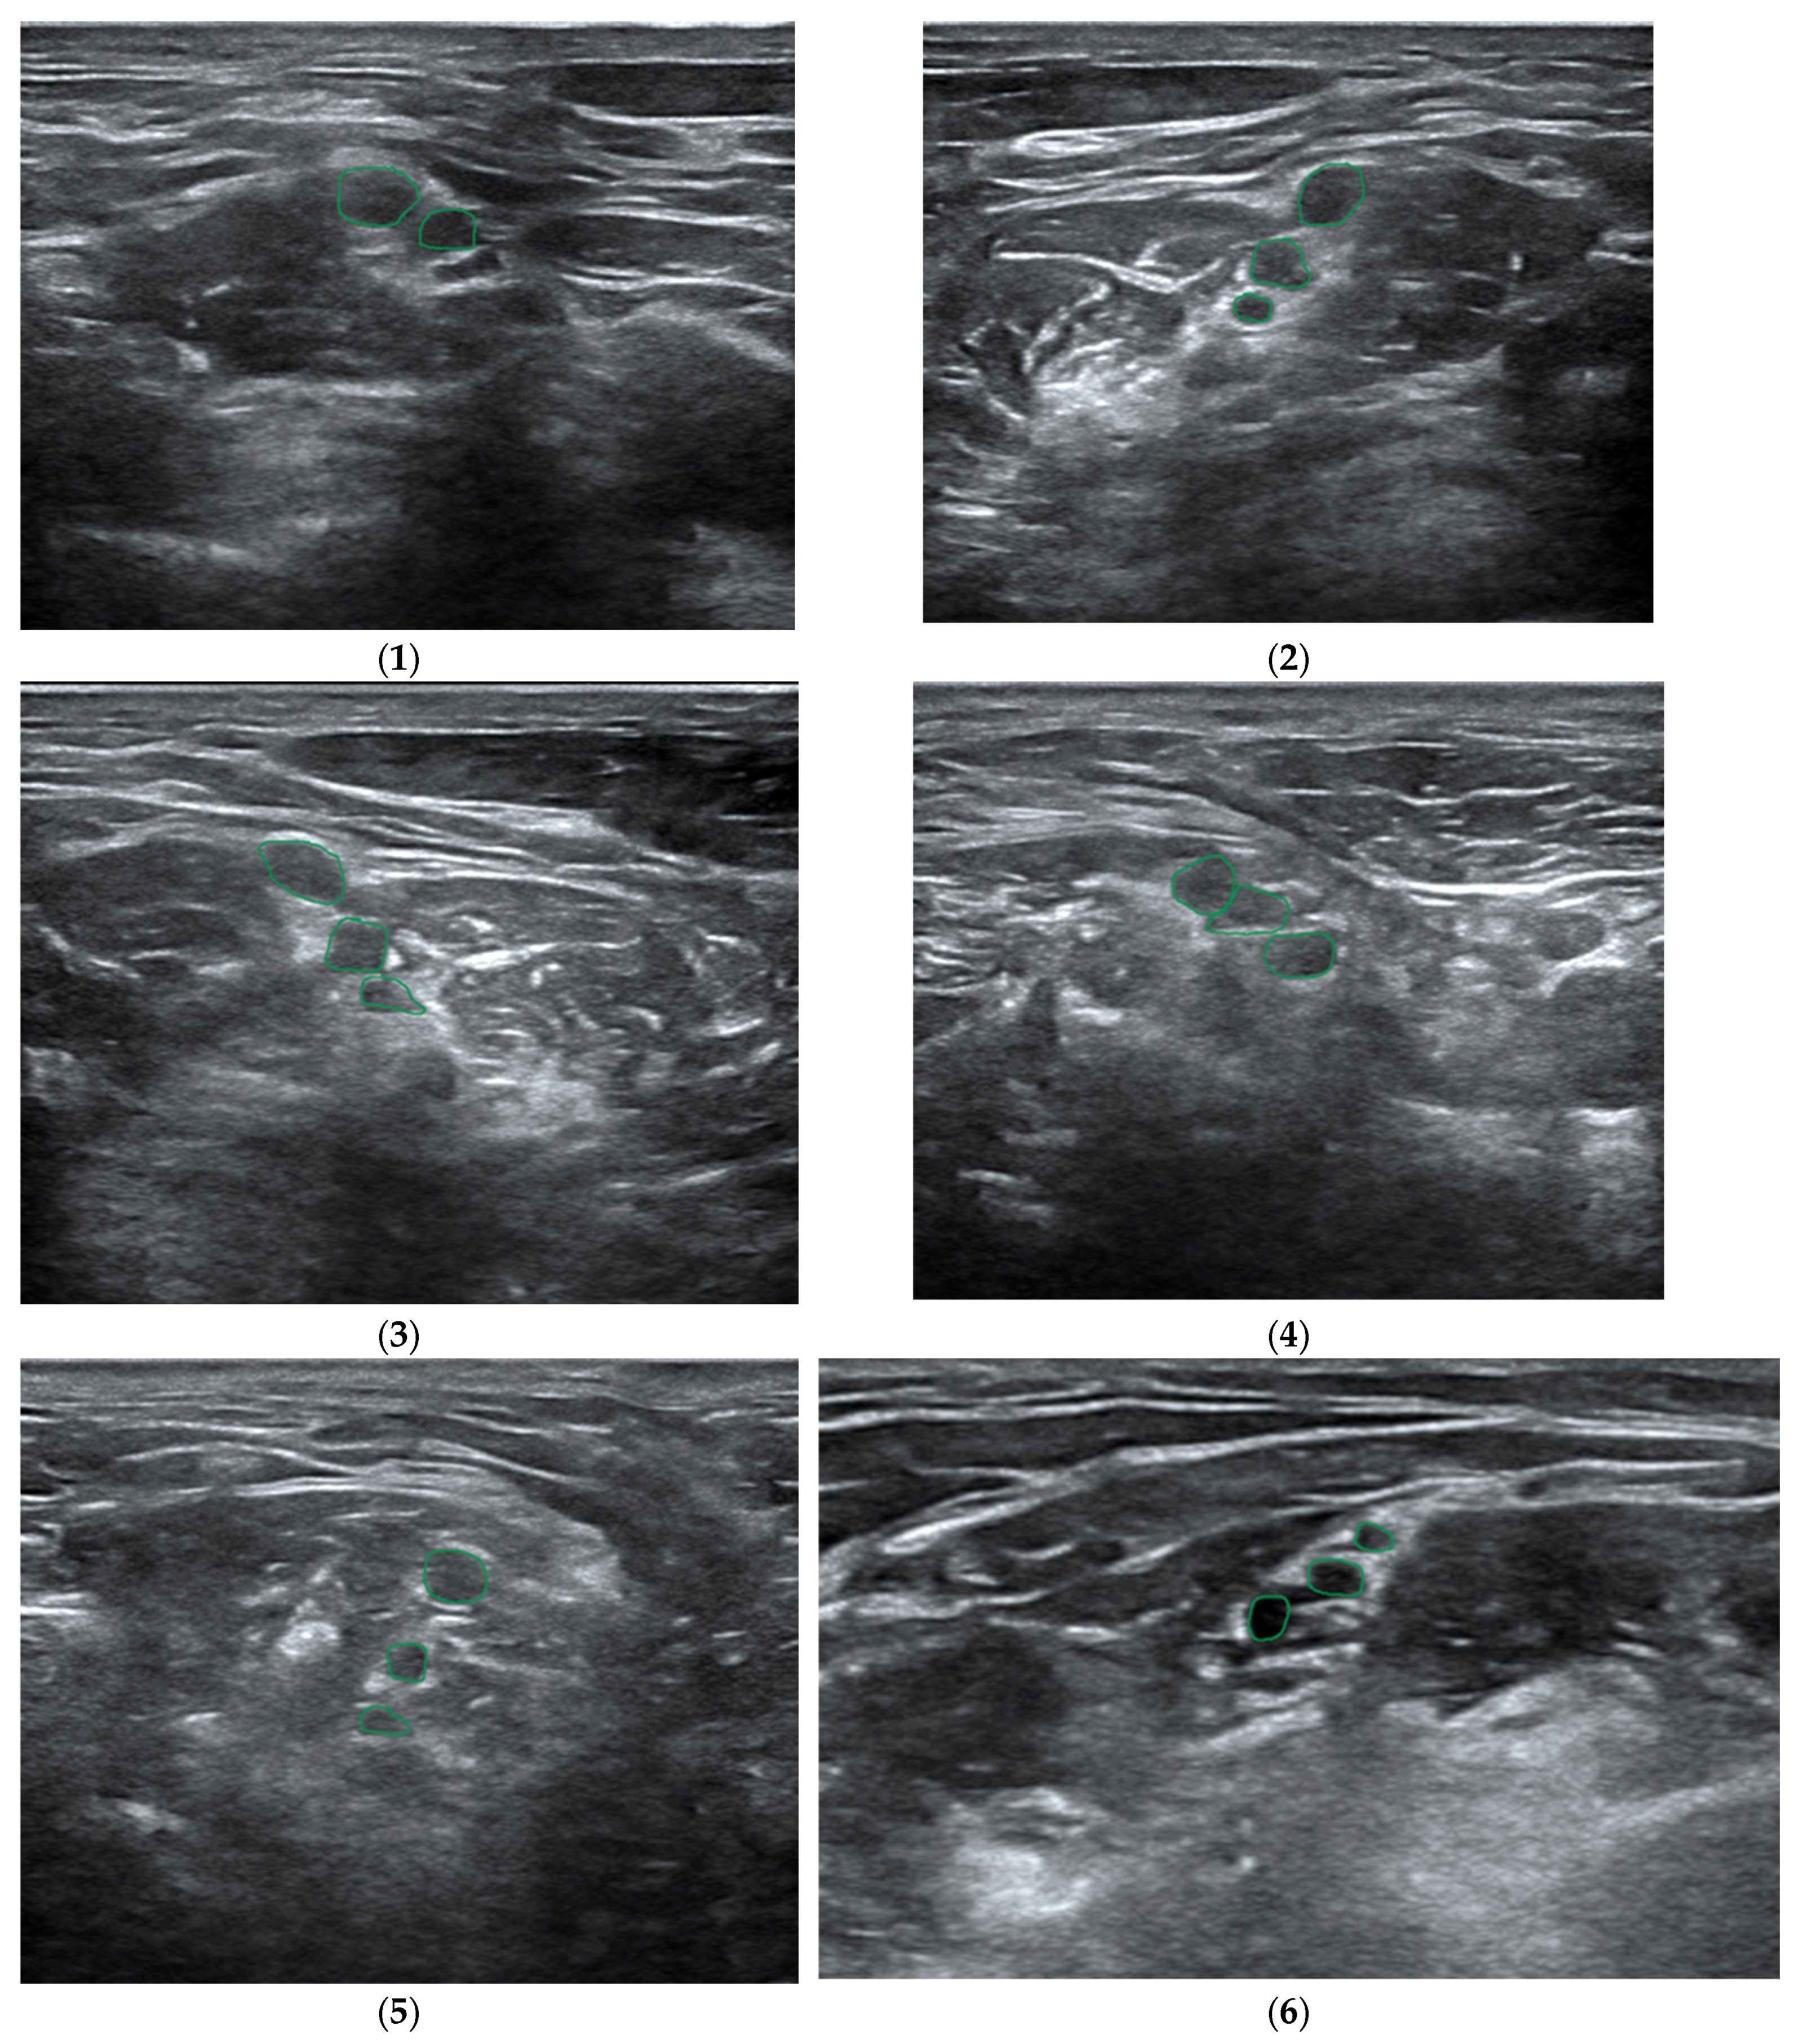

- Bowness, J.; Varsou, O.; Turbitt, L.; Burkett-St Laurent, D. Identifying anatomical structures on ultrasound: Assistive artificial intelligence in ultrasound-guided regional anesthesia. Clin. Anat. 2021, 34, 802–809. [Google Scholar] [CrossRef] [PubMed]

- Bowness, J.; Macfarlane, A.; Burckett-St Laurent, D.; Harris, C.; Margetts, S.; Morecroft, M.; Phillips, D.; Rees, T.; Sleep, N.; Vasalauskaite, A.; et al. Evaluation of the impact of assistive artificial intelligence on ultrasound scanning for regional anesthesia. Br. J. Anaesth. 2023, 130, 226–233. [Google Scholar] [CrossRef]

- Bowness, J.; Burckett-St Laurent, D.; Hernandez, N.; Keane, P.A.; Lobo, C.; Margetts, S.; Moka, E.; Pawa, A.; Rosenblatt, M.; Sleep, N.; et al. Assistive artificial intelligence for ultrasound image interpretation in regional anesthesia: An external validation study. Br. J. Anaesth. 2023, 130, 217–225. [Google Scholar] [CrossRef]